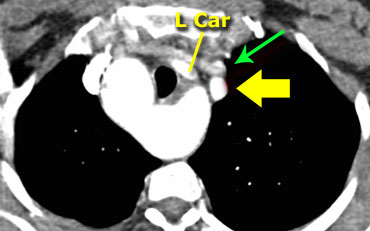

On the left a patient with a right arch with an aberrant left subclavian (indicated by the yellow arrow).

Scroll through the images on the left.

Again you have to realize that the axial CT-images have a ‘view from feet’.

Which vessels are indicated by the yellow and green arrow?

There is a right arch and the left subclavian artery is the last branch of the aortic arch, indicating that this is an aberrant left subclavian.

Medially to the left subclavian artery we see the left common carotid, that originates from the right side and has an oblique course to the left.

The yellow arrow indicates the azygos vein.

The green arrow indicates the left superior intercostal vein, a normal variant, that we will discuss later.

Same patient.

Posterior oblique view of volume rendered image to show the aberrant left subclavian artery.